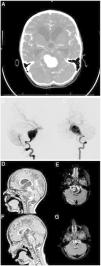

A girl aged 4 years was brought to the emergency department for assessment intense headache and vomiting the onset of which was followed by an episode of loss of consciousness and hypotonia that lasted 5 min. The patient presented with pallor and a Glasgow Coma Scale of 14 points. The mother reported that the patient had suffered from chronic headache for one year. The findings of a CT scan (Fig. 1A) prompted placement of an external ventricular drain. The angiogram (Fig. 1B and C) revealed the presence of an aneurysm in the basilar artery.

(A) The CT scan showed subarachnoid haemorrhage and obstructive hydrocephalus.

Cerebral angiogram. Left vertebral artery series: (B) lateral view and (C) anteroposterior view. Giant fusiform aneurysm in the two lower thirds of the basilar artery. Treatment options like parent artery sacrifice or stent-assisted reconstruction were ruled out on account of the age of the patient and anatomical considerations.

T1-weighted and FLAIR (fluid-attenuated inversion recovery) MRI images: (D) and (E) immediate postoperative period, and (F) and (G) 6 months after surgery. The images show a progressive reduction of the aneurysmal pouch and partial resolution of mass effect and obstructive hydrocephalus.

Parent artery sacrifice and stent-assisted reconstruction were ruled out as treatment options like were ruled out on account of the age of the patient and anatomical considerations. Flow reversal in the parent artery was considered the optimal approach, as the balloon occlusion test of the single left vertebral (with extreme hypoplasia of the right vertebral artery), was performed under neurophysiological monitoring and achieved an adequate deviation of basilar flow. Thus, the aneurysm was managed through endovascular occlusion of the left vertebral artery past the posterior cerebellar artery. An MRI scan was performed after the endovascular intervention (Fig. 1D–G). The patient was discharged at 34 days free of neurologic sequelae.